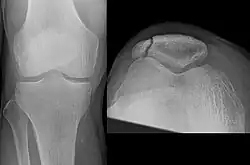

| A fracture of the patella seen on a lateral view | |

The patella can break in various ways depending on the way it is injured, and into two or more pieces.[1] Types include transverse, the most common, with one fracture line;[5] marginal; osteochondral; and the rare vertical type, or stellate, where a direct compression force gives rise to a comminuted pattern.[5][7] Patella fractures can be further classified as displaced, where the broken ends of bone do not line up correctly and separate by more than 2mm, or undisplaced and stable where pieces of bone remain in contact with each other.[1][7] If fragments of patella bone stick out from the skin it is known as an open patella fracture, and closed if the overlying skin is intact.[1]

Transverse fracture of patella -

Comminuted fracture of patella -

Osteochondral fracture of patella -

Vertical patella fracture